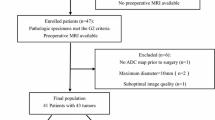

Briefly, 187 consecutive 68Ga-DOTATOC PET/MRI scans performed from March 2018 to June 2020 at IRCCS San Raffaele Scientific Institute in gastroenteropancreatic (GEP) NET patients were initially considered in this study and then selected according to the following inclusion criteria: (1) availability of simultaneous 68Ga-DOTATOC PET/MR scan with a dedicated MRI study on the abdomen, (2) surgical intervention for primary PanNET and availability of histological data.

Exclusion criteria were: (1) simultaneous MRI acquired without contrast agent and performed only for anatomical coregistration of PET images, (2) PET/MRI study performed for reasons other than staging purpose, (3) primary NETs outside the pancreatic gland, and (4) no availability of histological data derived by surgical intervention for primary PanNET. Sixteen patients met the inclusion criteria and were then included in the study (Fig. 1). This relative low number of patients is coherent with the incidence of PanNETs and related to the retrospective design of the study and the rarity of PanNETs.